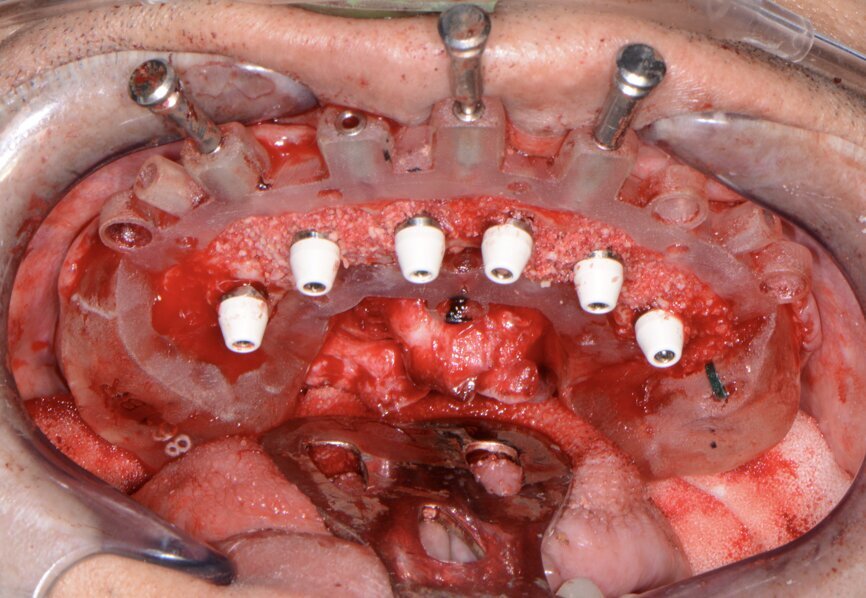

Fig. 13: Implants with corresponding multi-unit abutments.

A baseline Implant Stability Quotient reading was taken of these implants utilising the Penguin RFA unit (Aseptico). Since the initial readings were all above 70 and the quality of bone after levelling was good, multi-unit abutments (OCO Biomedical) were tightened into the Engage dental implants at 25 Ncm, followed by temporary cylinders at 15 Ncm. Any residual areas around the implants or in the sockets were grafted with a cortical mineralised and demineralised bone grafting material to optimise the area for regeneration (Fig. 13).